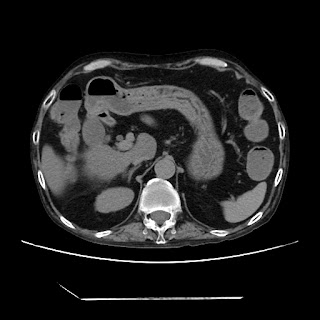

A 58 years old man with....

HRCT done on 17Mar16